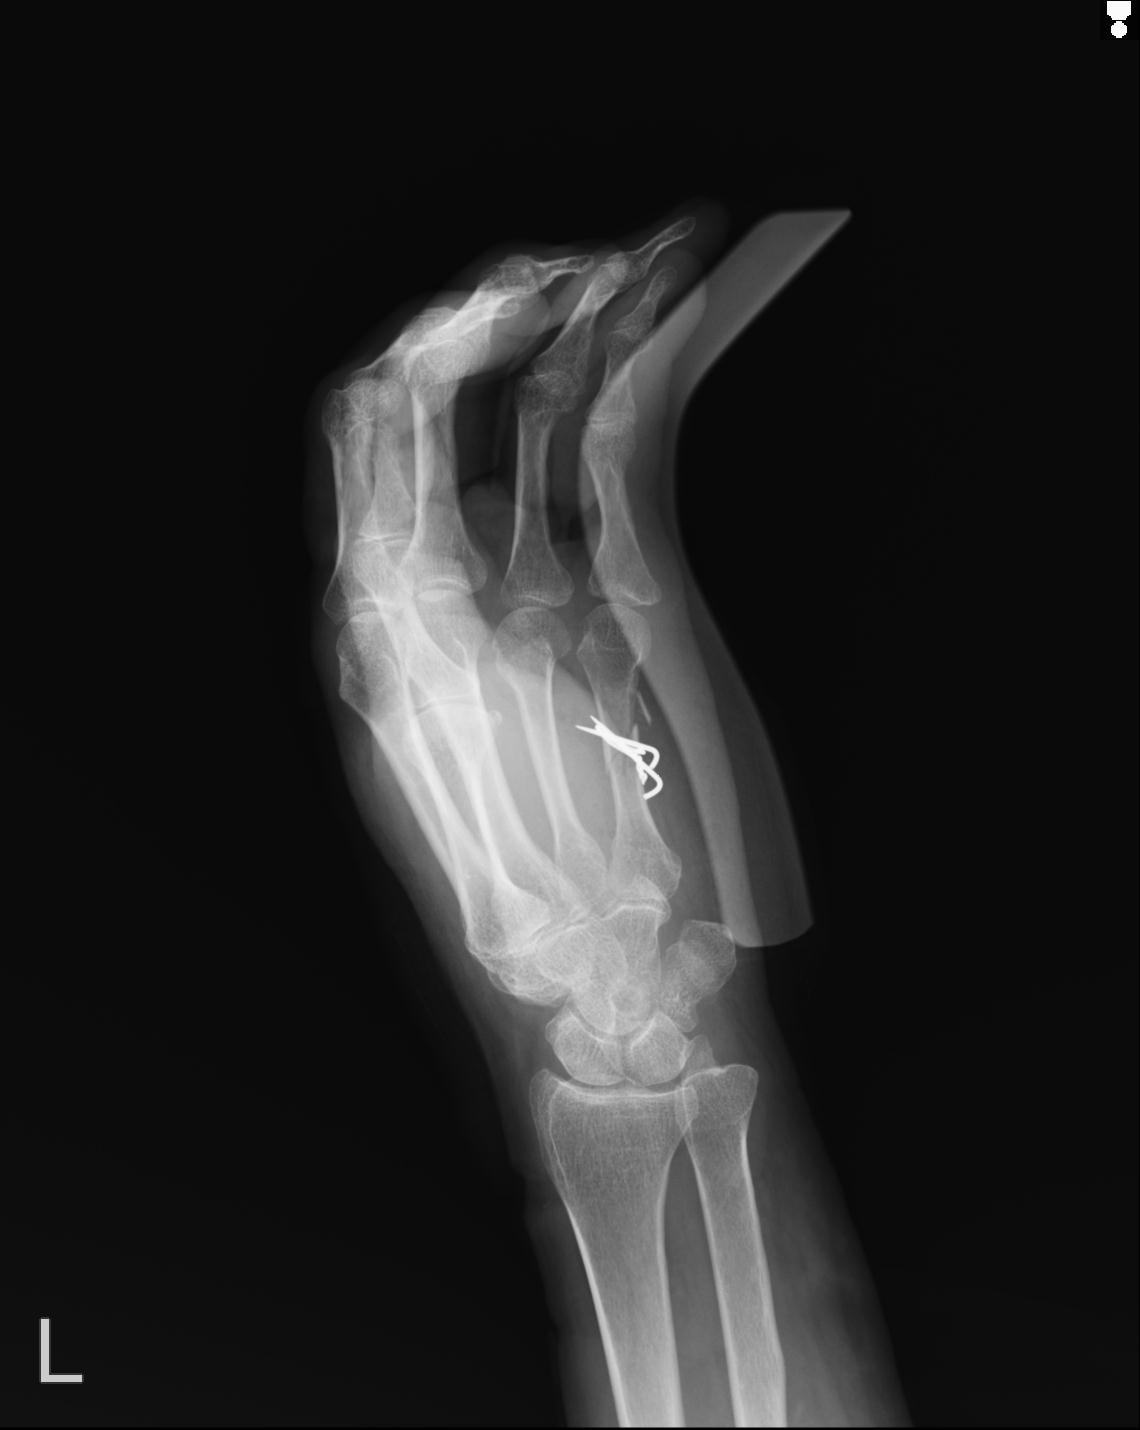

102766 1/5 1/12 左手関節 4R 28歳男性 左橈骨遠位端